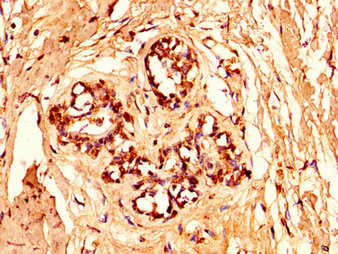

• IHC image of CSB-PA010378OA96nforHU diluted at 1:50 and staining in paraffin-embedded human breast cancer performed on a Leica BondTM system. After dewaxing and hydration, antigen retrieval was mediated by high pressure in a citrate buffer (pH 6.0). Section was blocked with 10% normal goat serum 30min at RT. Then primary antibody (1% BSA) was incubated at 4°C overnight. The primary is detected by a biotinylated secondary antibody and visualized using an HRP conjugated SP system.